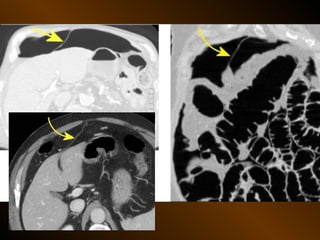

• X QUANG CẮT LỚP ĐIỆN TOÁN

– Mật độ

– Vị trí

– Nguyên nhân

TỤ DỊCH KHU TRÚ

• X QUANG QUY ƯỚC

– Tụ dịch ? – khối u ?

• SIÊU ÂM

– Phản âm, chất chứa, vỏ bọc ?

– Mật độ, bắt cản quang ?